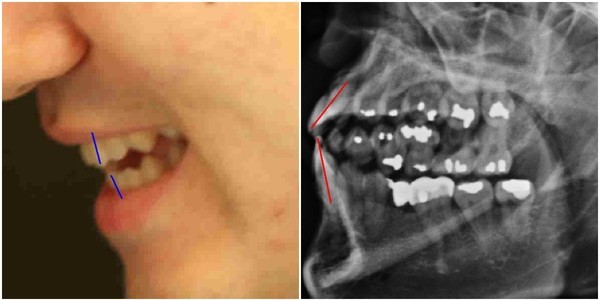

양승오 박사 등은 2012년 2월22일 박주신씨에 대한 공개신검 직후부터 언론을 통해 공개된 주신씨의 허리 부분 MRI 및 주신씨의 치아가 보이는 엑스레이 사진 등을 근거로, 주신씨가 대리신검 혹은 영상자료 바꿔치기 등의 방법으로 병역을 기피했다는 의혹을 제기하고 있다.

의혁투가 공개한 소견서는 아시아근골격학회 사무총장을 맡고 있는 스리 안드리아니 우토모 교수가 작성한 것으로, 박주신씨가 지난해 7월, 영국 출국 비자를 발급받기 위해 연세대 세브란스병원에서 촬영한 엑스레이(A)와, 2011년 12월 촬영된 자생병원 엑스레이(B)를 동일인의 것으로 볼 수 없다는 의학적 소견을 담고 있다.

의혁투는 아시아근골격학회에 보낸 의견 조회서에서, 박주신씨 명의의 두 엑스레이에서 나타나는 대표적 차이점인 ▲경추7번 및 흉추1번 척추골(극상돌기) ▲우측 늑골 1번의 ‘석회화 현상’ ▲전체적인 흉곽의 형태 ▲쇄골 형태의 차이 ▲하행 대동맥의 음영 등에 대해 질의했다.

이에 대해 우토모 교수는 위의 모든 항목에서, “두 엑스레이는 서로 다르다”는 견해를 분명히 밝혔다.

이에 대한 근거로 최 대표는 “2011년 12월 자생병원에서 찍은 엑스레이에서는 우측 제1늑골에 석회화 소견이 발견되고, 흉추 1번 극상돌기 역시 수직방향으로 배열돼 있지만, 공군 엑스레이와 비자발급용 세브란스병원 엑스레이에서는 석회화 현상이 발견되지 않았고, 극상돌기 역시 오른쪽 방향으로 배열돼 있다”고 설명했다.

- ▲ ▲박주신의 자생병원 X-Ray(왼쪽)과 공군 X-Ray(오른쪽). 자생병원의 엑스레이에서는 오른쪽 제1늑골부위에 '석회화'현상이 보이지만 공군엑스레이에선 보이지 않는다. ⓒ 뉴데일리DB

박주신씨의 자생병원 X-Ray를 보면, 오른쪽 제1 늑골부위에 ‘석회화’ 현상이 나타난다. 그러나 주신씨가 공군 입대 당시 찍은 X-Ray에는 이런 모습이 전혀 보이지 않는다.

이런 차이에 대해 양승오 박사의 변호인인 차기환 변호사 등은 "각각의 X-Ray를 찍은 사람이 동일인이 아니라는 것을 입증한다"고 설명했다.

‘극상돌기’의 경우에도 차이점은 명확히 드러난다.

변 호인 측은 “공군에서 찍은 엑스레이와 비자발급을 위해 찍은 엑스레이에서는 피사체의 제 1흉추 극상돌기가 오른쪽으로 휘어있지만, 자생병원에서 찍은 영상에서는 정방향으로 나온다”며, “박주신씨가 공군에 입대해 찍은 엑스레이와 세브란스 공개신검에서 나타난 피사체의 의학적 차이가 명확해 동일인이라고 인정할 수 없다”고 지적했다.

흉추를 비롯해 모든 척추에 존재하며, 흉추에 외상이나 수술, 질병 등이 없었던 근접한 기간 동안 촬영된 엑스레이에서 극상돌기의 형태가 명확하게 다를 경우, 다른 개체라고 판단할 의학적 근거가 된다.